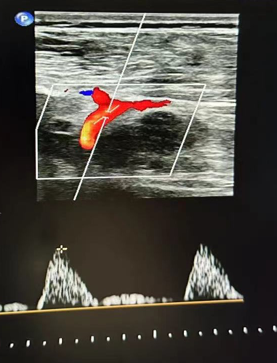

心功能室王璇主任会诊后,结合异常血流动力学特点,将目标锁定超声探查难点——胸骨遮挡的降主动脉胸段!建议行主动脉CT血管成像(CTA)检查以明确诊断。

CTA确诊:罕见畸形浮出水面

CTA结果印证了王璇主任的判断:患者降主动脉胸段(距锁骨下动脉约10厘米处)存在一处少见的先天性局部缩窄,并伴有远端扩张。这正是导致患者下肢血流灌注不足、多年感觉发凉的“元凶”——降主动脉缩窄,一种少见的血管发育畸形!